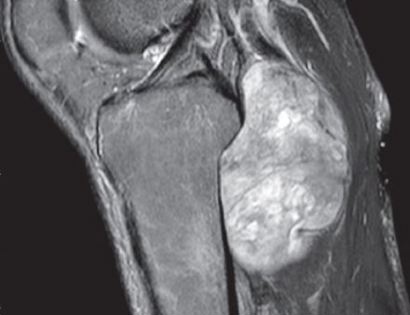

MRI of popliteal tumor

An MRI of the popliteal tumor is seen here. in the back of the knee, the tumor is the brightened image (right hand side of the image).